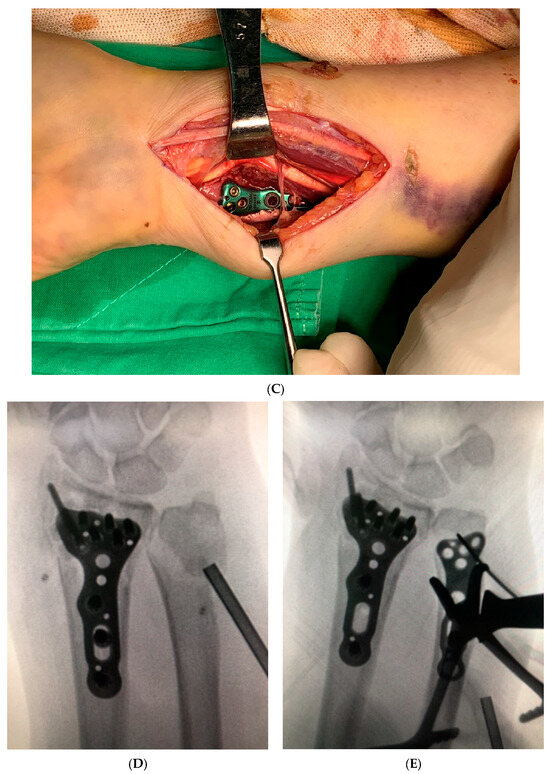

At the last follow-up, wrist flexion was 67 ± 11° and extension was 69 ± 13°. Forearm pronation was 81 ± 9° and supination was 79 ± 15°. Grip strength was 28.3 ± 11.5 kg, which was 88% of the uninjured opposite side. The mean Quick DASH score was 13.9 ± 11.5. The mean VAS during activity was 0.5 ± 0.9. The postoperative radiographic parameters were as follows: radial height: 10.8 ± 1.7 mm, radial inclination: 22.6 ± 3.7°, volar tilting: 4.0 ± 3.9°, and ulnar variance: −0.4 ± 1.4 mm. There were no cases of infection, neurovascular injury, or malreduction among these patients. However, impingement on the sigmoid notch of the radius caused by the ulnar implant, necessitating implant removal, was reported in two patients (15.4%) (Figure 4). Clinical results and radiographic parameters are summarized in Table 2.

Figure 4.

The figure shows a right distal forearm comminuted fracture pre- and post-operatively at nine months. The ulna implant was removed due to irritation, which caused bony erosion at the DRUJ. The white arrow indicates the erosion near the sigmoid notch.